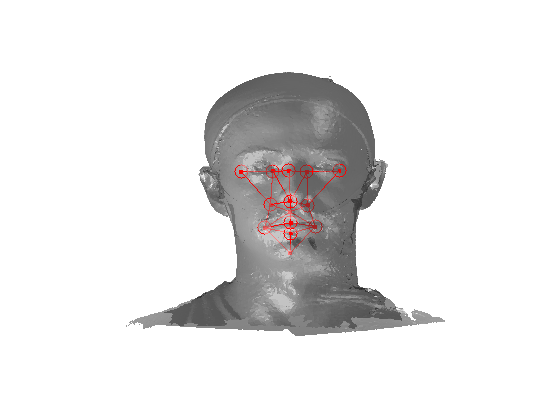

The landmarking system that we have implemented is a modified version of Creusot et al [23], where landmark candidates are generated via per-landmark scoring functions and then a configural model is iteratively fitted using a sample-consensus scheme. There are two parts to this algorithm: an off-line training scheme, shown in Fig. 5 and an online landmarking scheme, shown in 6. Note that we consider a sparse model of the face to consist of a set of landmarks in paticular configuration along with a set of landmark detector functions that score the likelihood of a particular vertex being a particular landmark, based on its local shape.

Referring to Fig. 5, our method is a supervised learning technique - landmarks are marked by hand on a set of training images. We used 279 faces (each different individuals) in the Face Recognition Grand Challenge (FRGC) dataset [26]. The landmarks used are described in table 1 111Some descriptions taken from www.facebase.org and can be seen on an example FRGC 3D face scan in Fig. 7.

Fig. 9 shows examples of the fitted model (trained on FRGC data) on the first four subjects in our Headspace training set. Note that the mean of the landmarks in the sparse model is centred on the orgin, and so the scan data is moved towards that and becomes frontal in pose. We note that other researchers [28] have used 3D landmark localisation to find the head, but often this only includes landmarks that are relatively easy to localise, namely inner eye corners and nose. Localising more landmarks over a wider facial area has a number of advantage in terms of cropping, pose normalisation and global 3D template warping, all of which are described later.